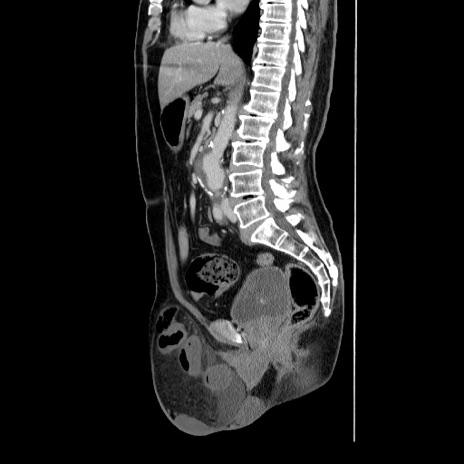

症例34(矢状断像)

【症例】60歳代 男性

【主訴】右鼠径部膨隆

【現病歴】1年程前より右鼠径部膨隆あり。自己にて還納可能だったため放置していた。3時間前より右鼠径部の脱出を認め、還納困難となり受診。

【身体所見】右鼠径部に小児頭大の膨隆あり。弾性硬であり、用手還納は困難。左鼠径部にも膨隆を認める。脱出はなし。